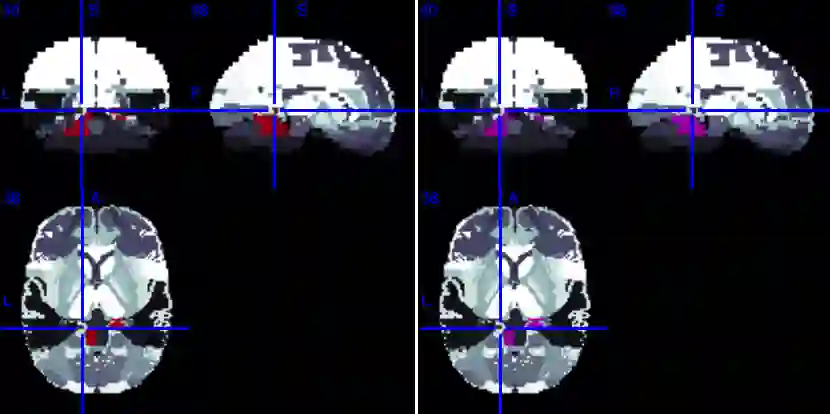

In this paper, we introduce a new Bayesian approach for analyzing task fMRI data that simultaneously detects activation signatures and background connectivity. Our modeling involves a new hybrid tensor spatial-temporal basis strategy that enables scalable computing yet captures nearby and distant intervoxel correlation and long-memory temporal correlation. The spatial basis involves a composite hybrid transform with two levels: the first accounts for within-ROI correlation, and second between-ROI distant correlation. We demonstrate in simulations how our basis space regression modeling strategy increases sensitivity for identifying activation signatures, partly driven by the induced background connectivity that itself can be summarized to reveal biological insights. This strategy leads to computationally scalable fully Bayesian inference at the voxel or ROI level that adjusts for multiple testing. We apply this model to Human Connectome Project data to reveal insights into brain activation patterns and background connectivity related to working memory tasks.